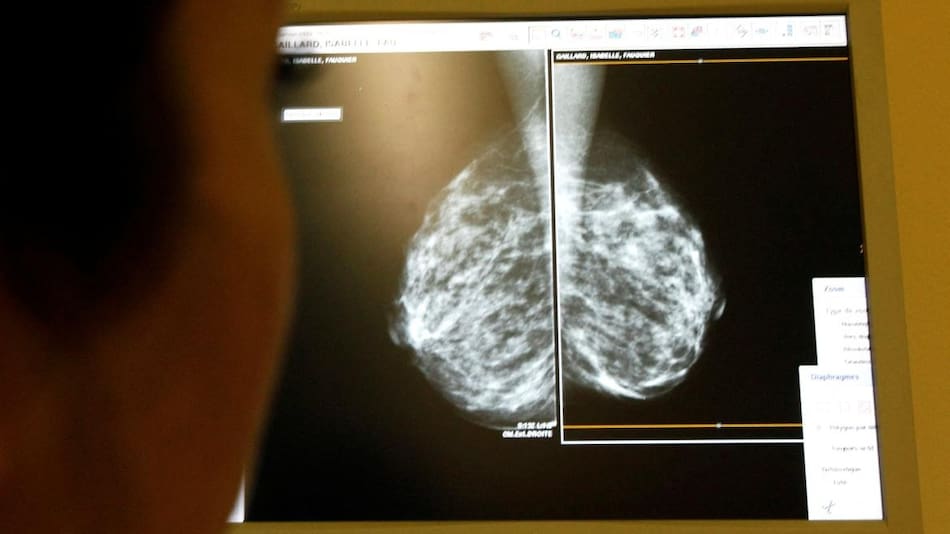

Cáncer de pulmón. Foto: Unsplash

Su utilización es múltiple ya que se utiliza para tratar el cáncer de piel, de pulmón de células no pequeñas, linfoma de Hodgkin, cáncer de cabeza y cuello, de vejiga, de mama, de cuello uterino, colorrectal, de endometrio, de esófago y de estómago, entre una treintena de indicaciones.